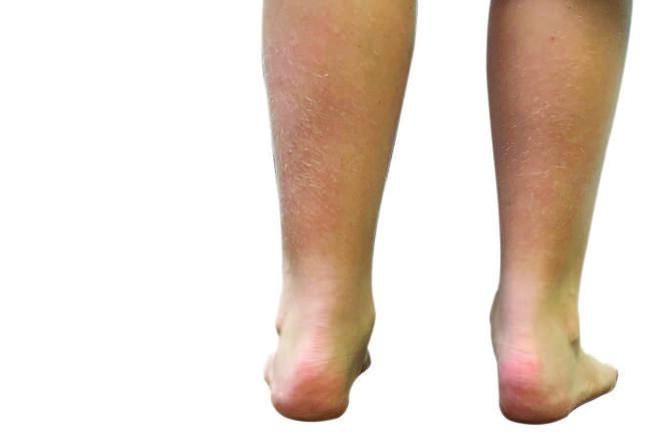

Sever’s disease, or calcaneal apophysitis, is a common cause of heel pain in the pediatric population. The patient will present with a chief concern of pain in the posterior aspect of the heel, either brought on by activity or occurring after the activity itself. While this is commonplace in pediatric sports medicine, in my private practice, I have recently noticed the condition present in a wide variety of children and foot types, regardless of engagement in sports, likely owing to lack of activity during the COVID-19 pandemic. Treatment options for this condition vary, most of the time depending on the clinician’s experience and personal success. In this article we aim to discuss the common presentation, appropriate examination, diagnosis, and treatment options for success.

Evaluation of foot position and type is necessary as both a pronated and a supinated foot can lead to increased force on the calcaneal apophysis. In the findings of a pronated foot or pediatric flatfoot, pronation at the subtalar joint can lead to dorsiflexion of the calcaneus, possibly giving mechanical advantage to the Achilles tendon, as seen in the above-referenced equinus. When this occurs and the child begins to increase activity, the force on the posterior calcaneus can increase, thus leading to the Sever’s condition.

In a cavus or supinated foot type, tightness in the posterior complex may be intrinsic. Also, a lack of pronation in the midfoot may lead to a decrease in shock absorption and dispersion throughout the foot. This shock absorption then focuses on the posterior calcaneus, potentially leading to the patient’s chief concern.